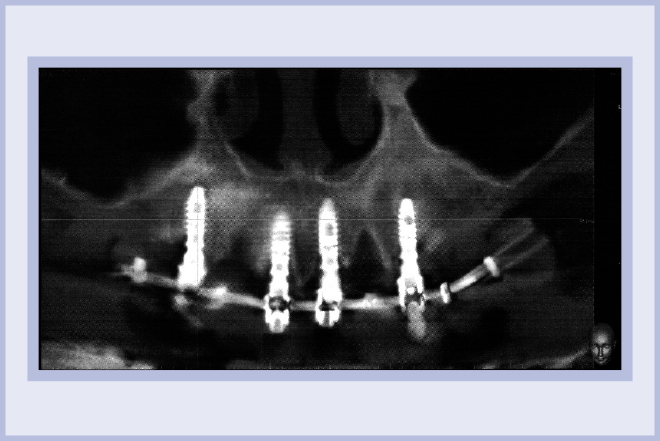

La semplicità della componentistica Leone ha permesso di completare l’intero trattamento in circa 6 ore e mezzo, consegnando alla paziente la protesi ultimata nella stessa giornata della chirurgia (Figg. 11-13).

- Fig. 13 – Immagine radiografica di controllo al termine dell’intervento